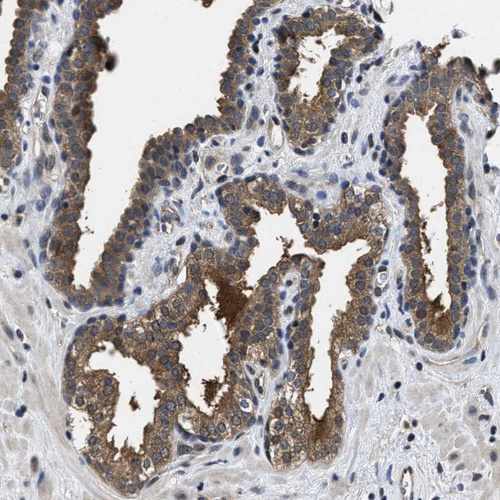

Immunohistochemical staining of human prostate shows moderate granular cytoplasmic positivity in glandular cells.